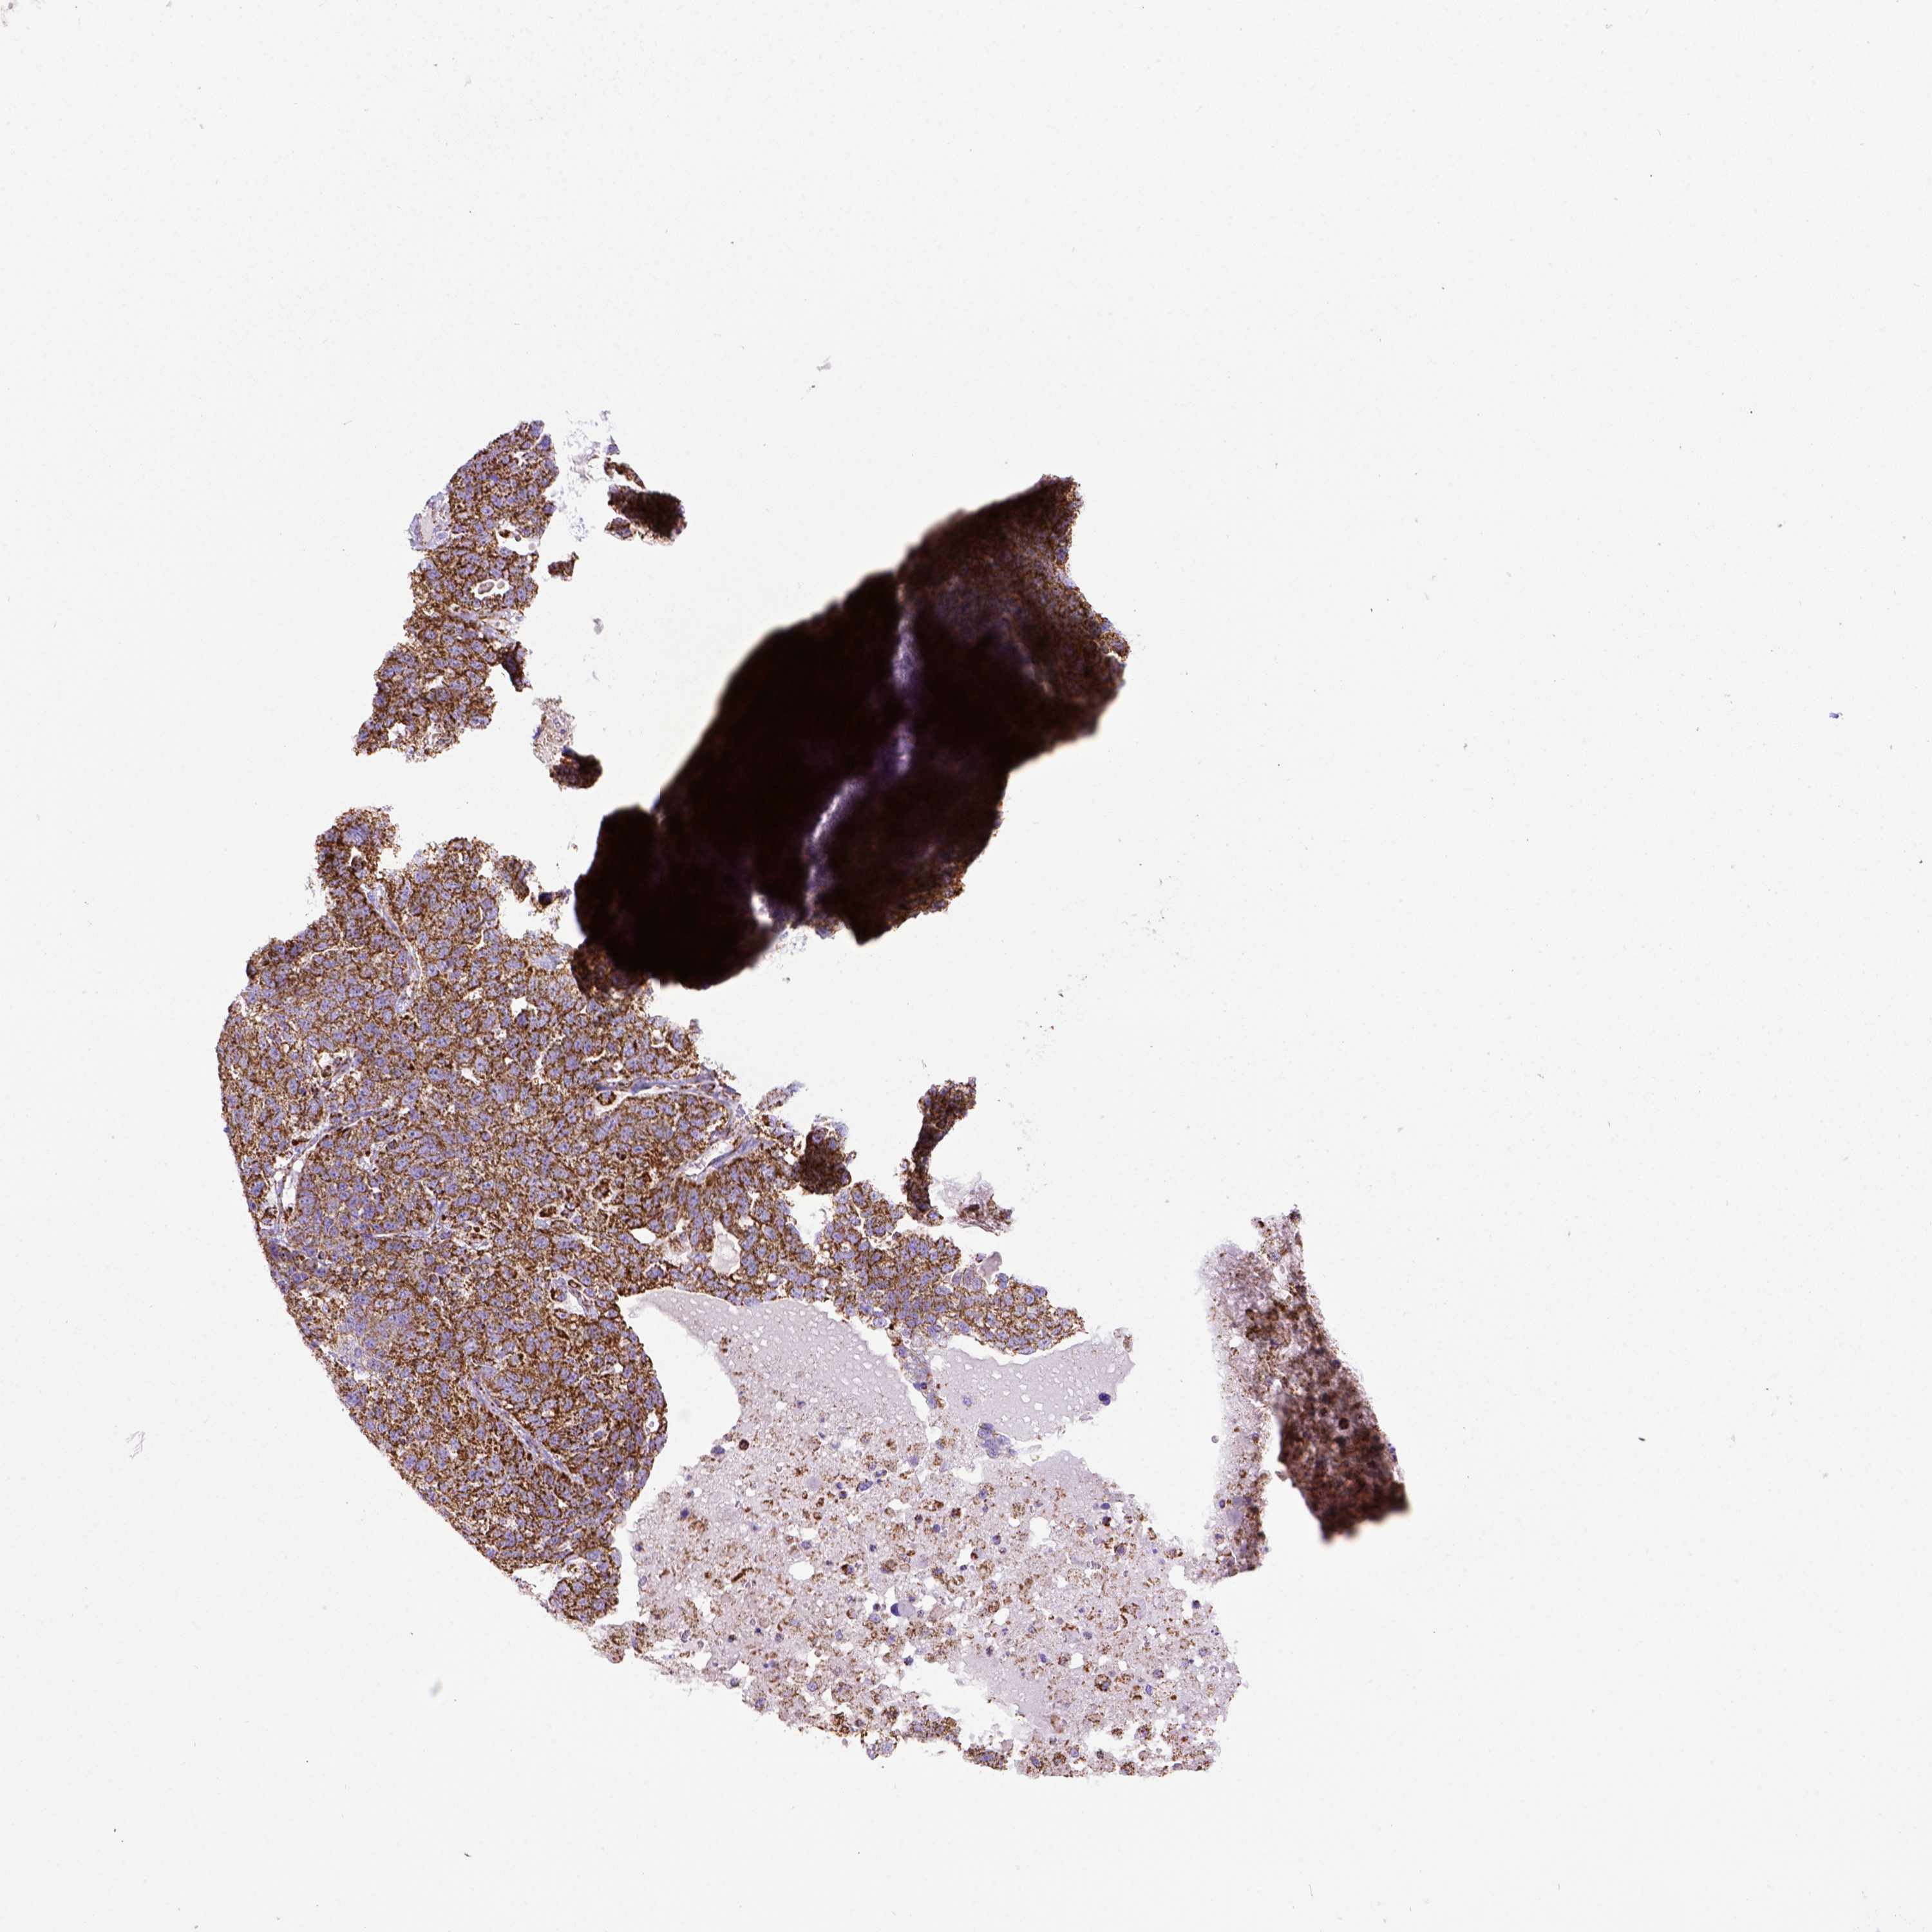

OVARIAN CANCER - Protein expressioni

A mouse-over function shows sample information and annotation data. Click on an image to view it in a full screen mode. Samples can be filtered based on level of antibody staining by selecting one or several of the following categories: high, medium, low and not detected. The assay and annotation is described here.

Note that samples used for immunohistochemistry by the Human Protein Atlas do not correspond to samples in the TCGA dataset.

Antibody stainingi

Antibody staining in the annotated cell types in the current human tissue is reported as not detected, low, medium, or high, based on conventional immunohistochemistry profiling in selected tissues. This score is based on the combination of the staining intensity and fraction of stained cells.

Each image is clickable and will lead to virtual microscopy that enables deeper exploration of all samples and also displays staining intensity scores, fraction scores and subcellular localization as well as patient and tissue information for each sample.

Antibody HPA069328

Antibody CAB016241

Staining

High

Medium

Low

Not detected

Intensity

Strong

Moderate

Weak

Negative

Quantity

>75%

75%-25%

<25%

None

Location

Nuclear

Cytoplasmic/membranous

Cytoplasmic/membranous,nuclear

Cystadenocarcinoma, serous, NOS

Cystadenocarcinoma, mucinous, NOS

Carcinoma, endometroid